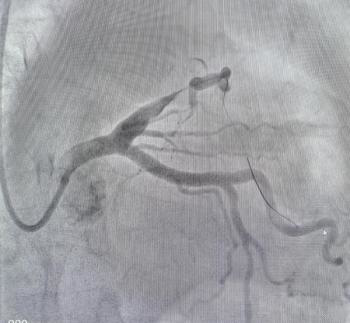

(逐渐开放闭塞血管)

李绍波主任当机立断,将指引导丝送入分支。在普通导丝无法通过的情况下,转而使用CTO导丝,成功抵达对角支的远端。随后,依次运用小球囊、大球囊、切割球囊及药物球囊进行操作。在最大型号4.0的药物球囊完成血管扩张后,介入室内的人员均感到紧张情绪得以缓解。手术效果良好,患者的心率逐步稳定,呼吸困难的状况亦有所改善。